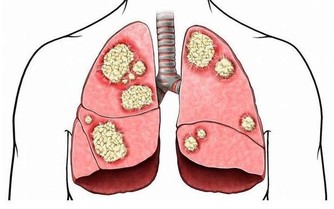

據美國紐約一家專門從事癌癥研究的權威機構透露,中國和日本婦女乳腺癌的發病率比西方低得多,這是為什麼呢?

科學家在比較了世界各國的三餐食譜後得出結論:是由於中國和日本婦女多吃大白菜的緣故。

調查資料表明,每10萬名婦女中,每年乳腺癌的發病率為:中國9人,日本21人,北歐84人,美國91人。

實驗證明,大白菜所含有的許多物質、具有防癌抗癌的作用,因此在美國國立癌癥研究所、發表的防癌食品排行榜中、將白菜排在僅次於大蒜的後面,名列第二。。

其次,大白菜含有一種叫做吲哚-3-甲醇的化合物,其含量約佔大白菜重量的0.01%,它能促進人體產生一種重要的酶,這種酶能夠有效抑製癌細胞的生長和分裂。

據測算,每天吃1磅大白菜,或白菜榨汁,每天飯後服200-300克,就能吸收到500毫克這種化合物,達到預防癌癥的目的。

科學家們認為,硒通過吞噬細胞的功能、能夠影響癌細胞的能量代謝、和幹擾癌細胞的蛋白合成,從而抑製癌癥,還能夠影響化學致癌物的代謝,使它們失去致癌的活性。